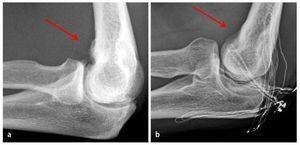

Fig. 16 Para la documentación de los resultados de la intervención quirúrgica se realiza un control radiológico en dos planos del codo antes del alta del paciente. a, b) Se pudieron extraer los osteofitos humerales presentes en el preoperatorio (flechas).

- Control radiológico postoperatorio en 2 planos (fig. 16).